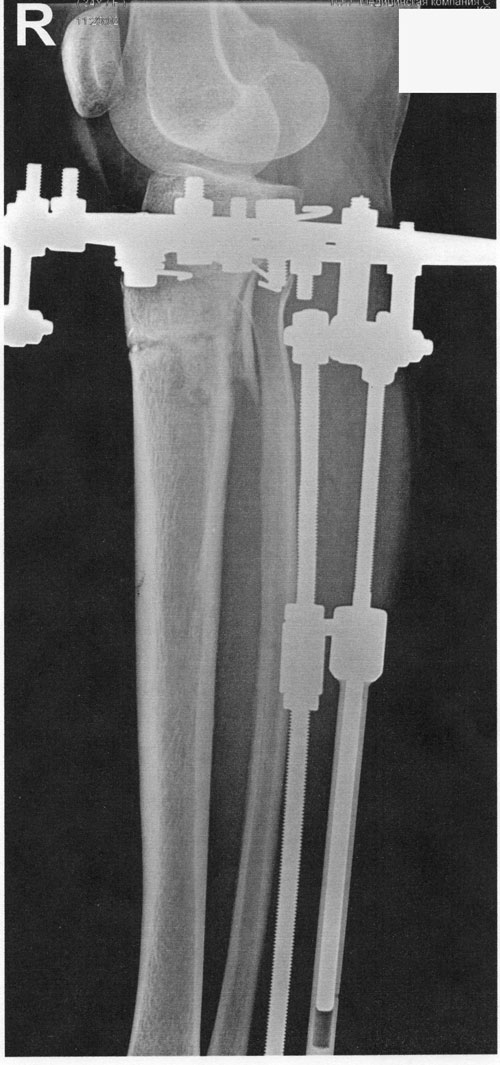

рентген в 20 дней после операции.

рентген в 60 дней.

Сращение идёт хорошо. Делаем рентген в 90 дней и готовимся к снятию.

рентген в 90 дней.

Здравствуйте, Iskorka! По рентгену, сращение отличное, ждём на снятие аппаратов.

РЕНТГЕН В ДЕНЬ СНЯТИЯ АППАРАТОВ.

Рентген в сравнении (ортопедическая ось) ДО - ПОСЛЕ операции.